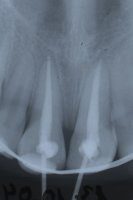

Ein 9-jähriges Mädchen kam eine Stunde nach einem Sturz, bei welchem es den linken oberen mittleren Schneidezahn komplett herausgeschlagen und den rechten massiv traumatisiert hatte (wackelte sehr stark), in unser Praxis (Röntgenbild Abb. 3). Der herausgeschlagene Zahn wurde sofort replantiert und beide mittleren Schneidezähne in die ursprüngliche Lage zurückversetzt und in dieser Situation mittels eines Drahtbogens an die Nachbarzähne fixiert (Röntgenbild Abb. 4).

Die verletzten Schneidezähne mussten beide wurzelbehandelt werden (Röntgenbild Abb. 5, siehe auch Kapitel Endodontie).